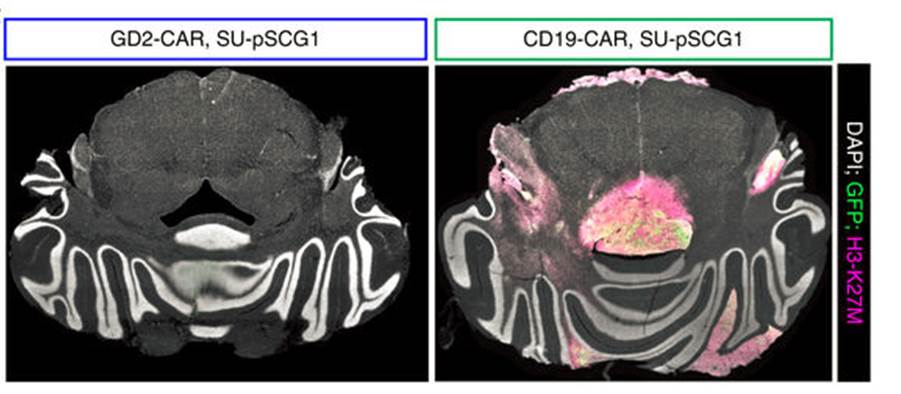

Figure 1. Immunofluorescence images of H3-K27M+ glioma cells implanted into the mouse central nervous system. Mice that received GD2-CAR T cells (left) had virtually undetected tumor cells, while tumors in mice that received a CAR T cells with an unrelated CAR (right) were free to expand. Adapted from Figure 4g (ref.4). Macmillan Publishers.

The researchers focused on a specific glioma type—diffuse intrinsic pontine glioma—that is associated with a K27M mutation in histone H3. Often aggressive and ‘universally fatal’, these tumors ‘diffuse’ along the brain stem, making surgical removal not an option. To better achieve a clinically relevant setup in their xenograft glioma mouse model, the researchers implanted patient-derived tumor cells in the spinal cord or the thalamus of the mice, and proceeded with infusion of the engineered CAR T cells 7–8 weeks after tumor establishment. In both situations the CAR T cells effectively ablated the vast majority of the tumor cells (Figure 1). However, mice with thalamic gliomas developed substantial toxicity, possibly due to local edema, highlighting the importance of the neuroanatomical location of this type of tumors when considering therapeutic strategies and monitoring for adverse effects.